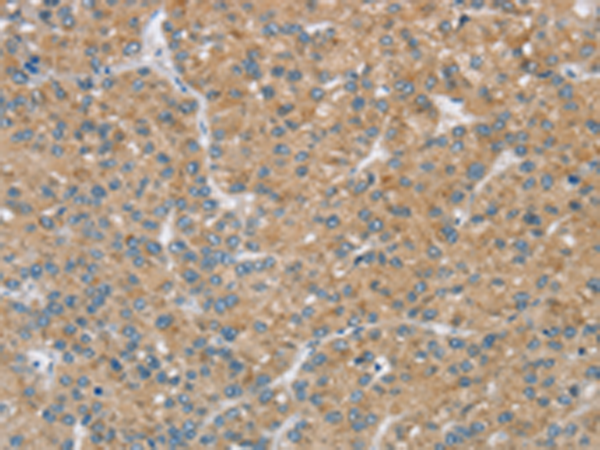

分类: 科研抗体货号: P12181别名: NCKX3应用: IHC反应种属: Human, Mouse, Rat